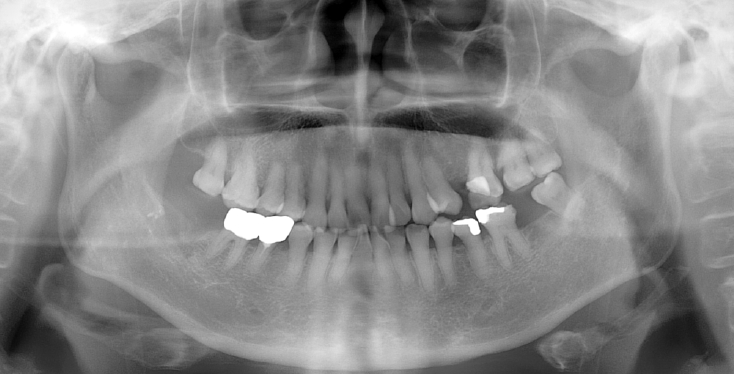

An 18-year-old male developed numbness in the right lower lip, gingiva, and chin following endodontic treatment of the mandibular right first molar (#46) at a military hospital 2 weeks ago. A panoramic radiograph and multi-detector computed tomography (MDCT) revealed extruded Calcipex II in proximity to the IAN (Fig. 6). Neurologic testing confirmed severe hypoesthesia in the right mentum region. Thermal discrimination was absent across a broad area of the right lower lip and chin. The patient’s subjective discomfort was rated as VAS 2. The patient underwent foreign body removal, nerve transposition, and bone grafting under general anesthesia (Fig. 7). At one-week postoperative follow-up, neurosensory testing showed little to no improvement. At the five-month follow-up, repeated neurosensory testing demonstrated meaningful improvement in directional discrimination and pin-pressure nociceptive discrimination, despite the continued presence of hypoesthesia. At the 17-month follow-up, testing revealed further improvement, including recovery of static light touch sensation, with overall symptoms classified as mild hypoesthesia. However, the patient reported worsening subjective discomfort, with a VAS 5, reflecting a discordance between objective sensory recovery and subjective symptom persistence.

Figure 6.

A. Pre-op panoramic radiograph of Case 4 patient. B. Pre-op MDCT of Case 4 patient